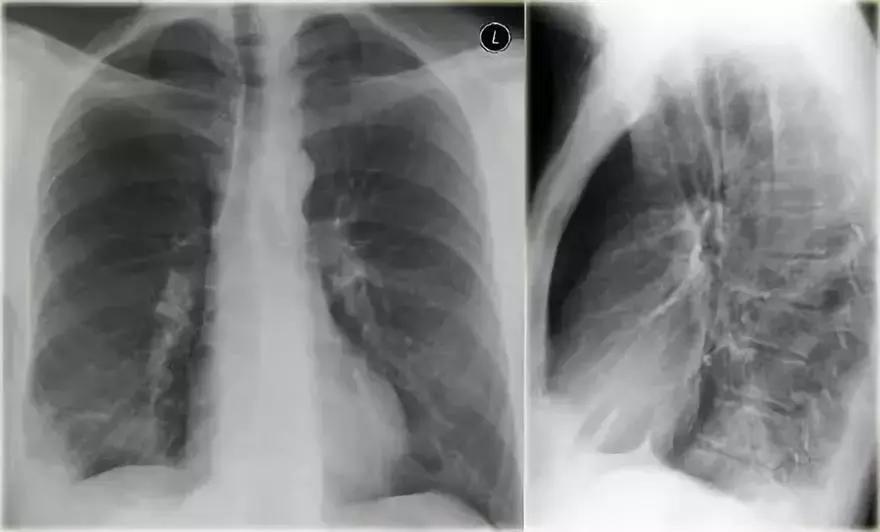

肺隔离症

肺隔离症是肺叶实变不常见的原因,属于先天性异常。

➢ 肺部肺功能部分不能和支气管树进行正常的信息传递,无法接受体循环提供的动脉血。

➢ 当细菌从孔氏孔移动时,病人会出现反复感染

➢ 箭头所示为从主动脉分离的供血动脉

图8 肺隔离症实变